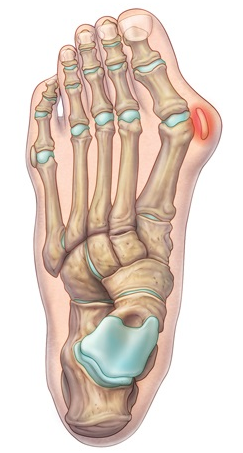

• Anatomia da superfície plantar da cabeça do 1° metatarso: